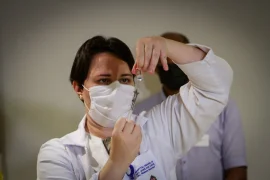

Drive-thru vacina idosos com mais de 80 anos contra a Covid-19 neste sábado (27)

'Drive thru' vacina 1.100 idosos com mais de 85 anos neste fim de semana

Vacinação de idosos acamados começa nesta segunda-feira (15)

Bauru terá vacinação 'drive thru' para idosos acima de 85 anos

Idosos acima de 90 anos começam a ser vacinados em Bauru

Estado de SP inicia vacinação de idosos acima de 85 anos de idade em fevereiro

Comunidades quilombolas começam a ser imunizadas contra a Covid-19 no estado de SP

Secretaria de Saúde inicia vacinação dos profissionais da 'linha de frente' em Bauru

Começa a imunização contra a Covid-19 no interior de SP; técnica em enfermagem é a primeira vacinada na região de Bauru